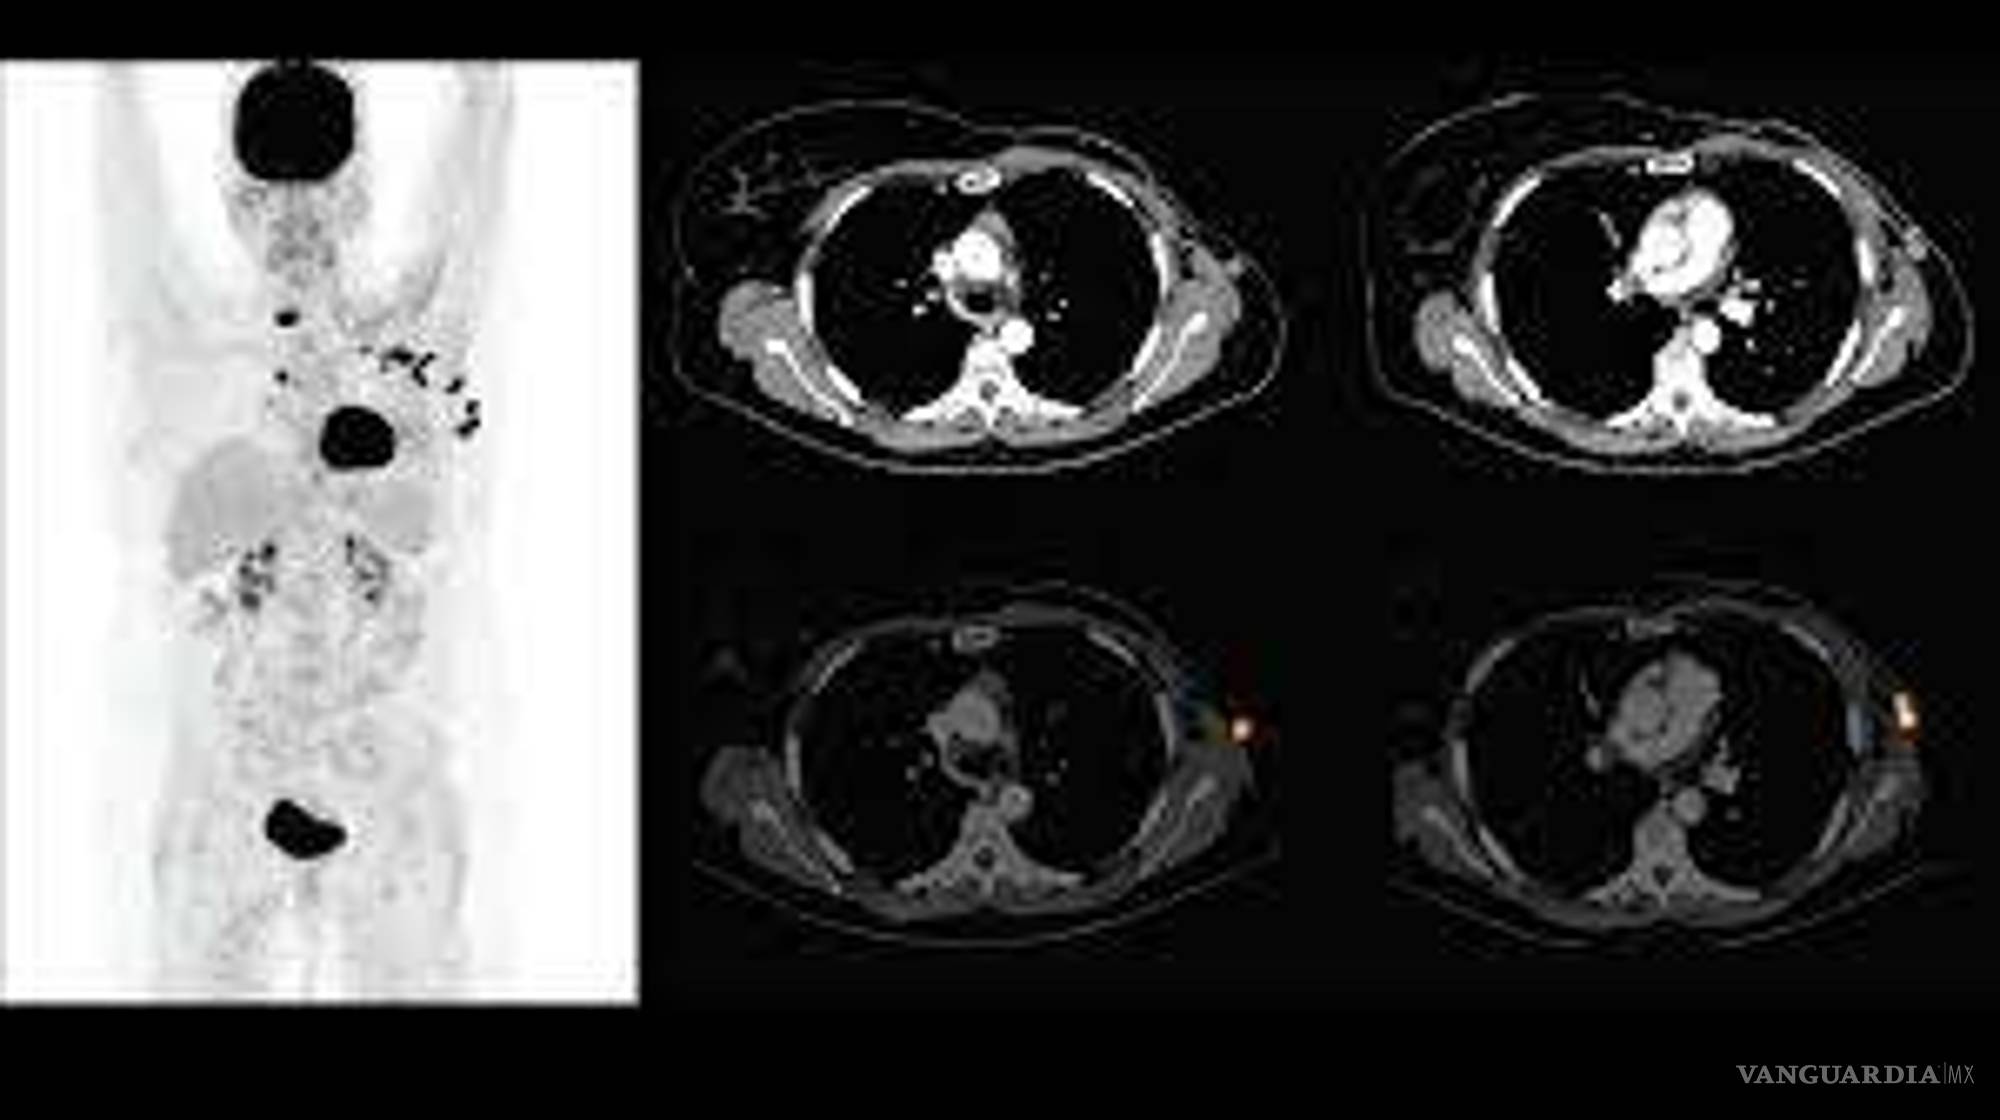

“Yo conozco mujeres que llevan seis meses sin recibir quimioterapias. Yo sé que las células mutan, y si pasa el tiempo son daños muy severos. No hay para un PET (tomografía por emisión de positrones). No hay para nada. Me han recetado estudios urgentes y no hay. Me han enviado hasta Monterrey a hacérmelo, y allá en Monterrey me dicen que no hay, que se descompuso la máquina. Fuera del área de oncología es excelente, pero fuera de ahí el trato es inhumano. Sí hay metátesis no voy a reparar en demandarlos”, dice la paciente.

De acuerdo con el testimonio, hay gente que tienen dos años esperando un PET y muchos pacientes se quedan callados. Luisa cuenta que una amiga murió hace algunos meses por falta de atención.

Después de enero del 2020, Idalia tenía que realizarse un PET para escanear su cuerpo y una vez más tuvo que viajar a la CDMX. La cita la pidió desde noviembre, pero le negaron el estudio que con un particular tiene un valor de 30 mil pesos.

Lo intentó en varias ocasiones y durante marzo, cuando inició la pandemia, le rechazaron la solicitud de estudio argumentando que estaban en enfrentando una epidemia. Ahora el estudio deberá hacérselo este septiembre, mes en que las autoridades del Hospital 20 de noviembre del ISSSTE en CDMX le dieron cita. Flor Idalia ahora tiene una sospecha en uno de sus pechos.

“Debí de haberme hecho el estudio más tarde en mayo. Es un escaneado que permite saber si hay metástasis o, en mi caso, una ligera sospecha que ahora tengo en mi pecho”, dice Idalia.